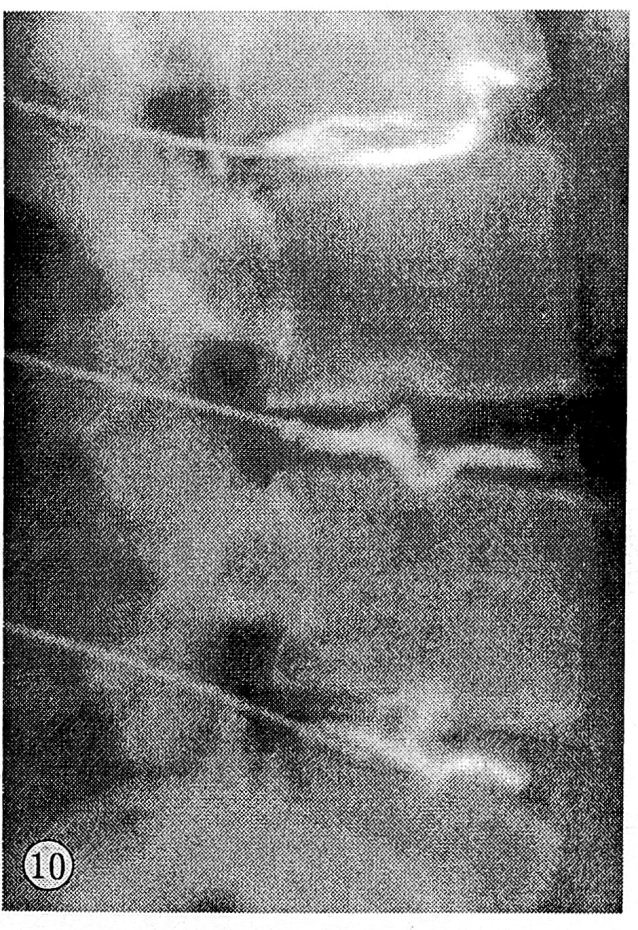

На дискограммах внутриспонгиозного типа отмечалось заполнение контрастным веществом грыж Шморля, т.е. дефектов спонгиозной ткани тела позвонка (см. рис. 10).

Рис. 10. Внутриспонгиозный тип дискограмм (грыжи Шморля L2, L4 позвонков).

В 17 случаях контрастное вещество не выходило за пределы склеротической каймы вокруг грыж Шморля. Остальные 5 случаев демонстрировали дальнейшее продвижение контрастного вещества в глубь тела позвонка на 2—5 мм. Мы располагаем также двумя наблюдениями внутриспонгиозного пролабирования студенистого ядра без признаков грыжи Шморля на стандартных спондилограммах (см. рис. 5 и 11). Емкость диска составляла 1,0—1,8 мл. Введение контрастного вещества не сопровождалось болью. Высота межтеловых промежутков была умеренно снижена.